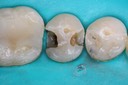

Photos of Clinical Operations

Drs. Peter Kearney, Terry McKay, John St. Germain, and Laurie Vanzella - Mentors